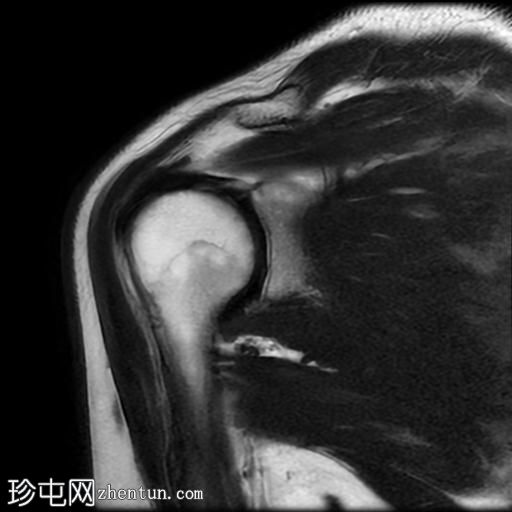

MRI

冠状位

T2加权像

T1加权像

冠状位PD加权像

脂肪抑制像

矢状位

PD加权像

肩袖钙化性肌腱炎:冈下肌腱上部纤维可见约7 x 14 mm的低信号病灶

冈上肌腱滑囊侧纤维可见轻度增高液体信号,提示肌腱病

肩峰II型

肩峰下滑囊可见轻度液体信号